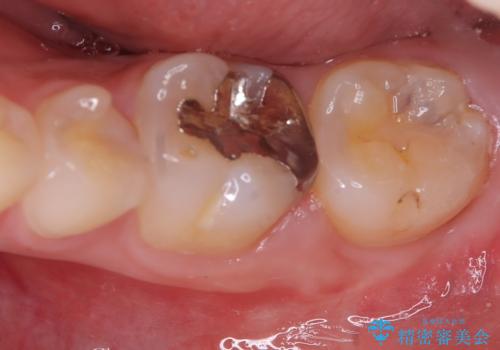

- 初診時にお口の中をチェックしたところ虫歯があり、大きさから部分的な詰め物のお話をしました。材料の特性を説明し、再び虫歯になりにくいセラミックインレーを選択されました。

セラミックインレー接着時にはラバーダム防湿を行いました。